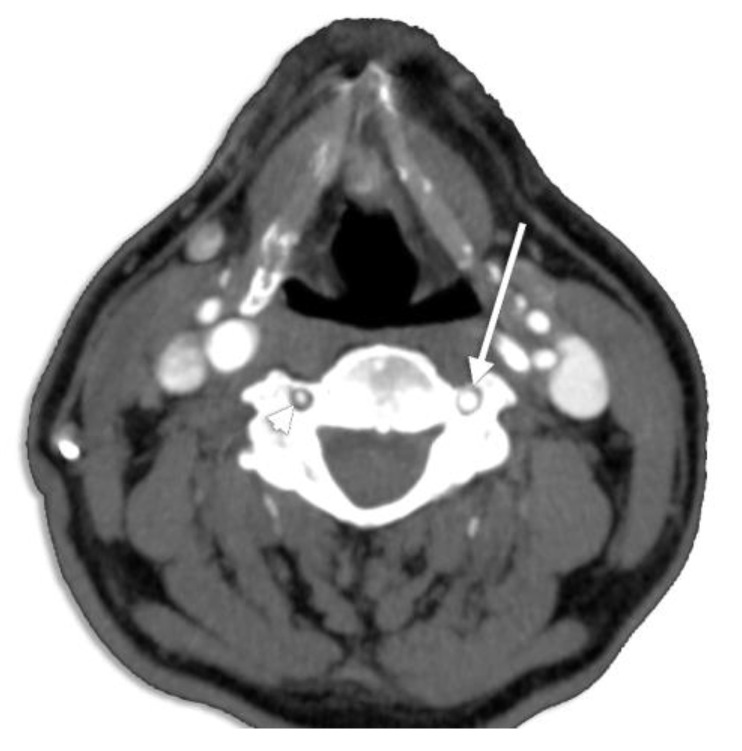

Gantwerker et al. [95] correlated VA’s diameter with the size of the TF; thus, a small TF may presume a hypoplastic or even an aplastic vessel (Figure 30). Hypoplastic VAs have been widely analyzed for their clinical appliance, being a predisposing factor for posterior circulation ischemia [96]. George and Laurian [97] reported a frequency of 5.7% for LVA hypoplasia and 8.8% for hypoplastic RVAs, without mentioning the hypoplastic segment (V1–V4) and including also the atretic arteries.

Figure 30.

Axial CT slice at the level of C4 viewed inferiorly. Right vertebral artery hypoplasia (arrowhead). Normoplastic left vertebral artery (arrow).